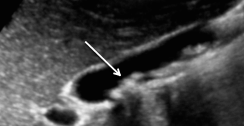

- Lithiases (fréquentes)